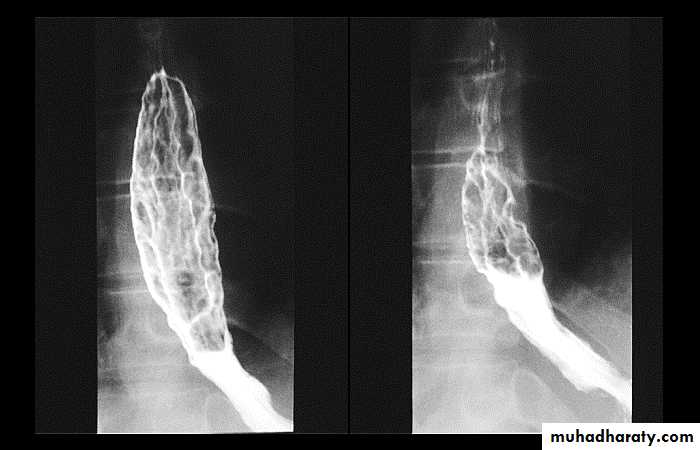

Esophageal Varieces

Dilatation of venous plexus in the wall of the esophagus due to increased pressure ( portal H.T.).

Important cause of Hematemesis .

Early changes seen in the mucosa (D.C.) loss of parallelism with thick and tortuous folds.

Later multiple small filling defects (fine cobble stone).

In advanced stage large filling defects ( coarse cobble stone ) .

7More advanced stage elongated and worm like filling defect .

The changes are seen at lower third and gastric fundus.